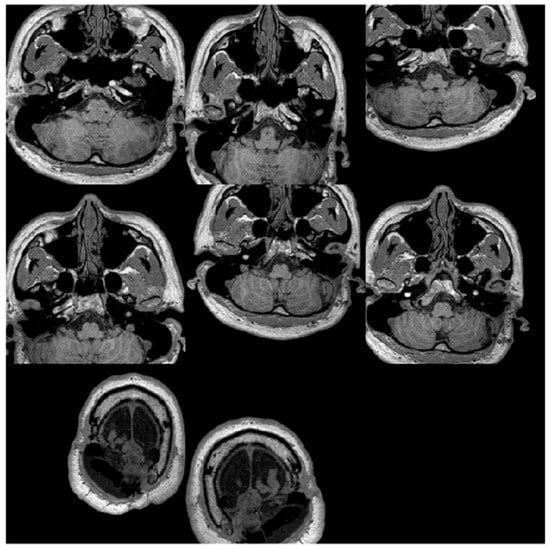

2.1. MRI Dataset

2.2. Image Pre-Processing

3.1. Image Pre-Processing